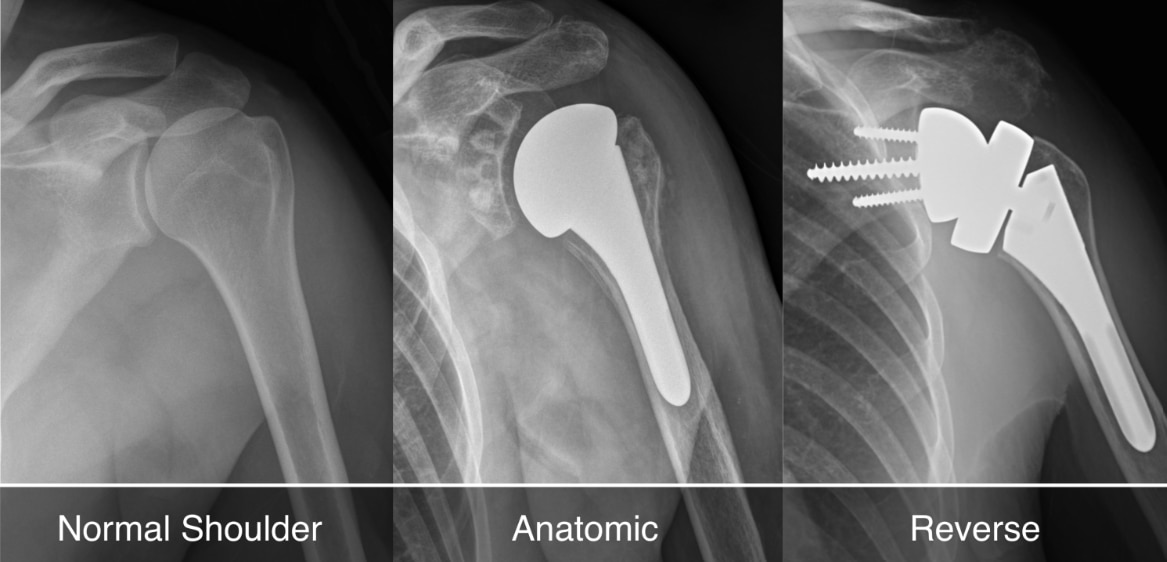

Shoulder Arthroplasty

Shoulder arthroplasty is a surgical procedure used to replace damaged or arthritic parts of the shoulder joint with artificial components. It is typically recommended for patients with severe osteoarthritis, complex fractures, or rotator cuff-related joint degeneration that limits mobility and causes chronic pain. At Rapha Sports and Regenerative Orthopaedics, our surgeons offer advanced shoulder replacement options tailored to each patient’s condition, lifestyle, and functional goals. Types of Shoulder Arthroplasty: Total Shoulder Replacement (Anatomic): Replaces both the ball (humeral head) and socket (glenoid) with prosthetic components. Best suited for patients with intact rotator cuff muscles and primary osteoarthritis. Reverse Shoulder Replacement: Reverses the normal anatomy of the shoulder by placing the ball component on the shoulder blade and the socket on the upper arm. Ideal for patients with rotator cuff tears, cuff tear arthropathy, or complex fractures. Hemiarthroplasty: Replaces only the ball portion of the joint. Often used in certain fractures or where the socket remains healthy. Partial/Stemless Shoulder Replacement: A bone-preserving option for select patients with less extensive damage, offering quicker recovery and less invasive techniques. Our multidisciplinary team ensures seamless care—from pre-operative planning to post-operative physiotherapy—focused on restoring function, reducing pain, and supporting long-term joint health.